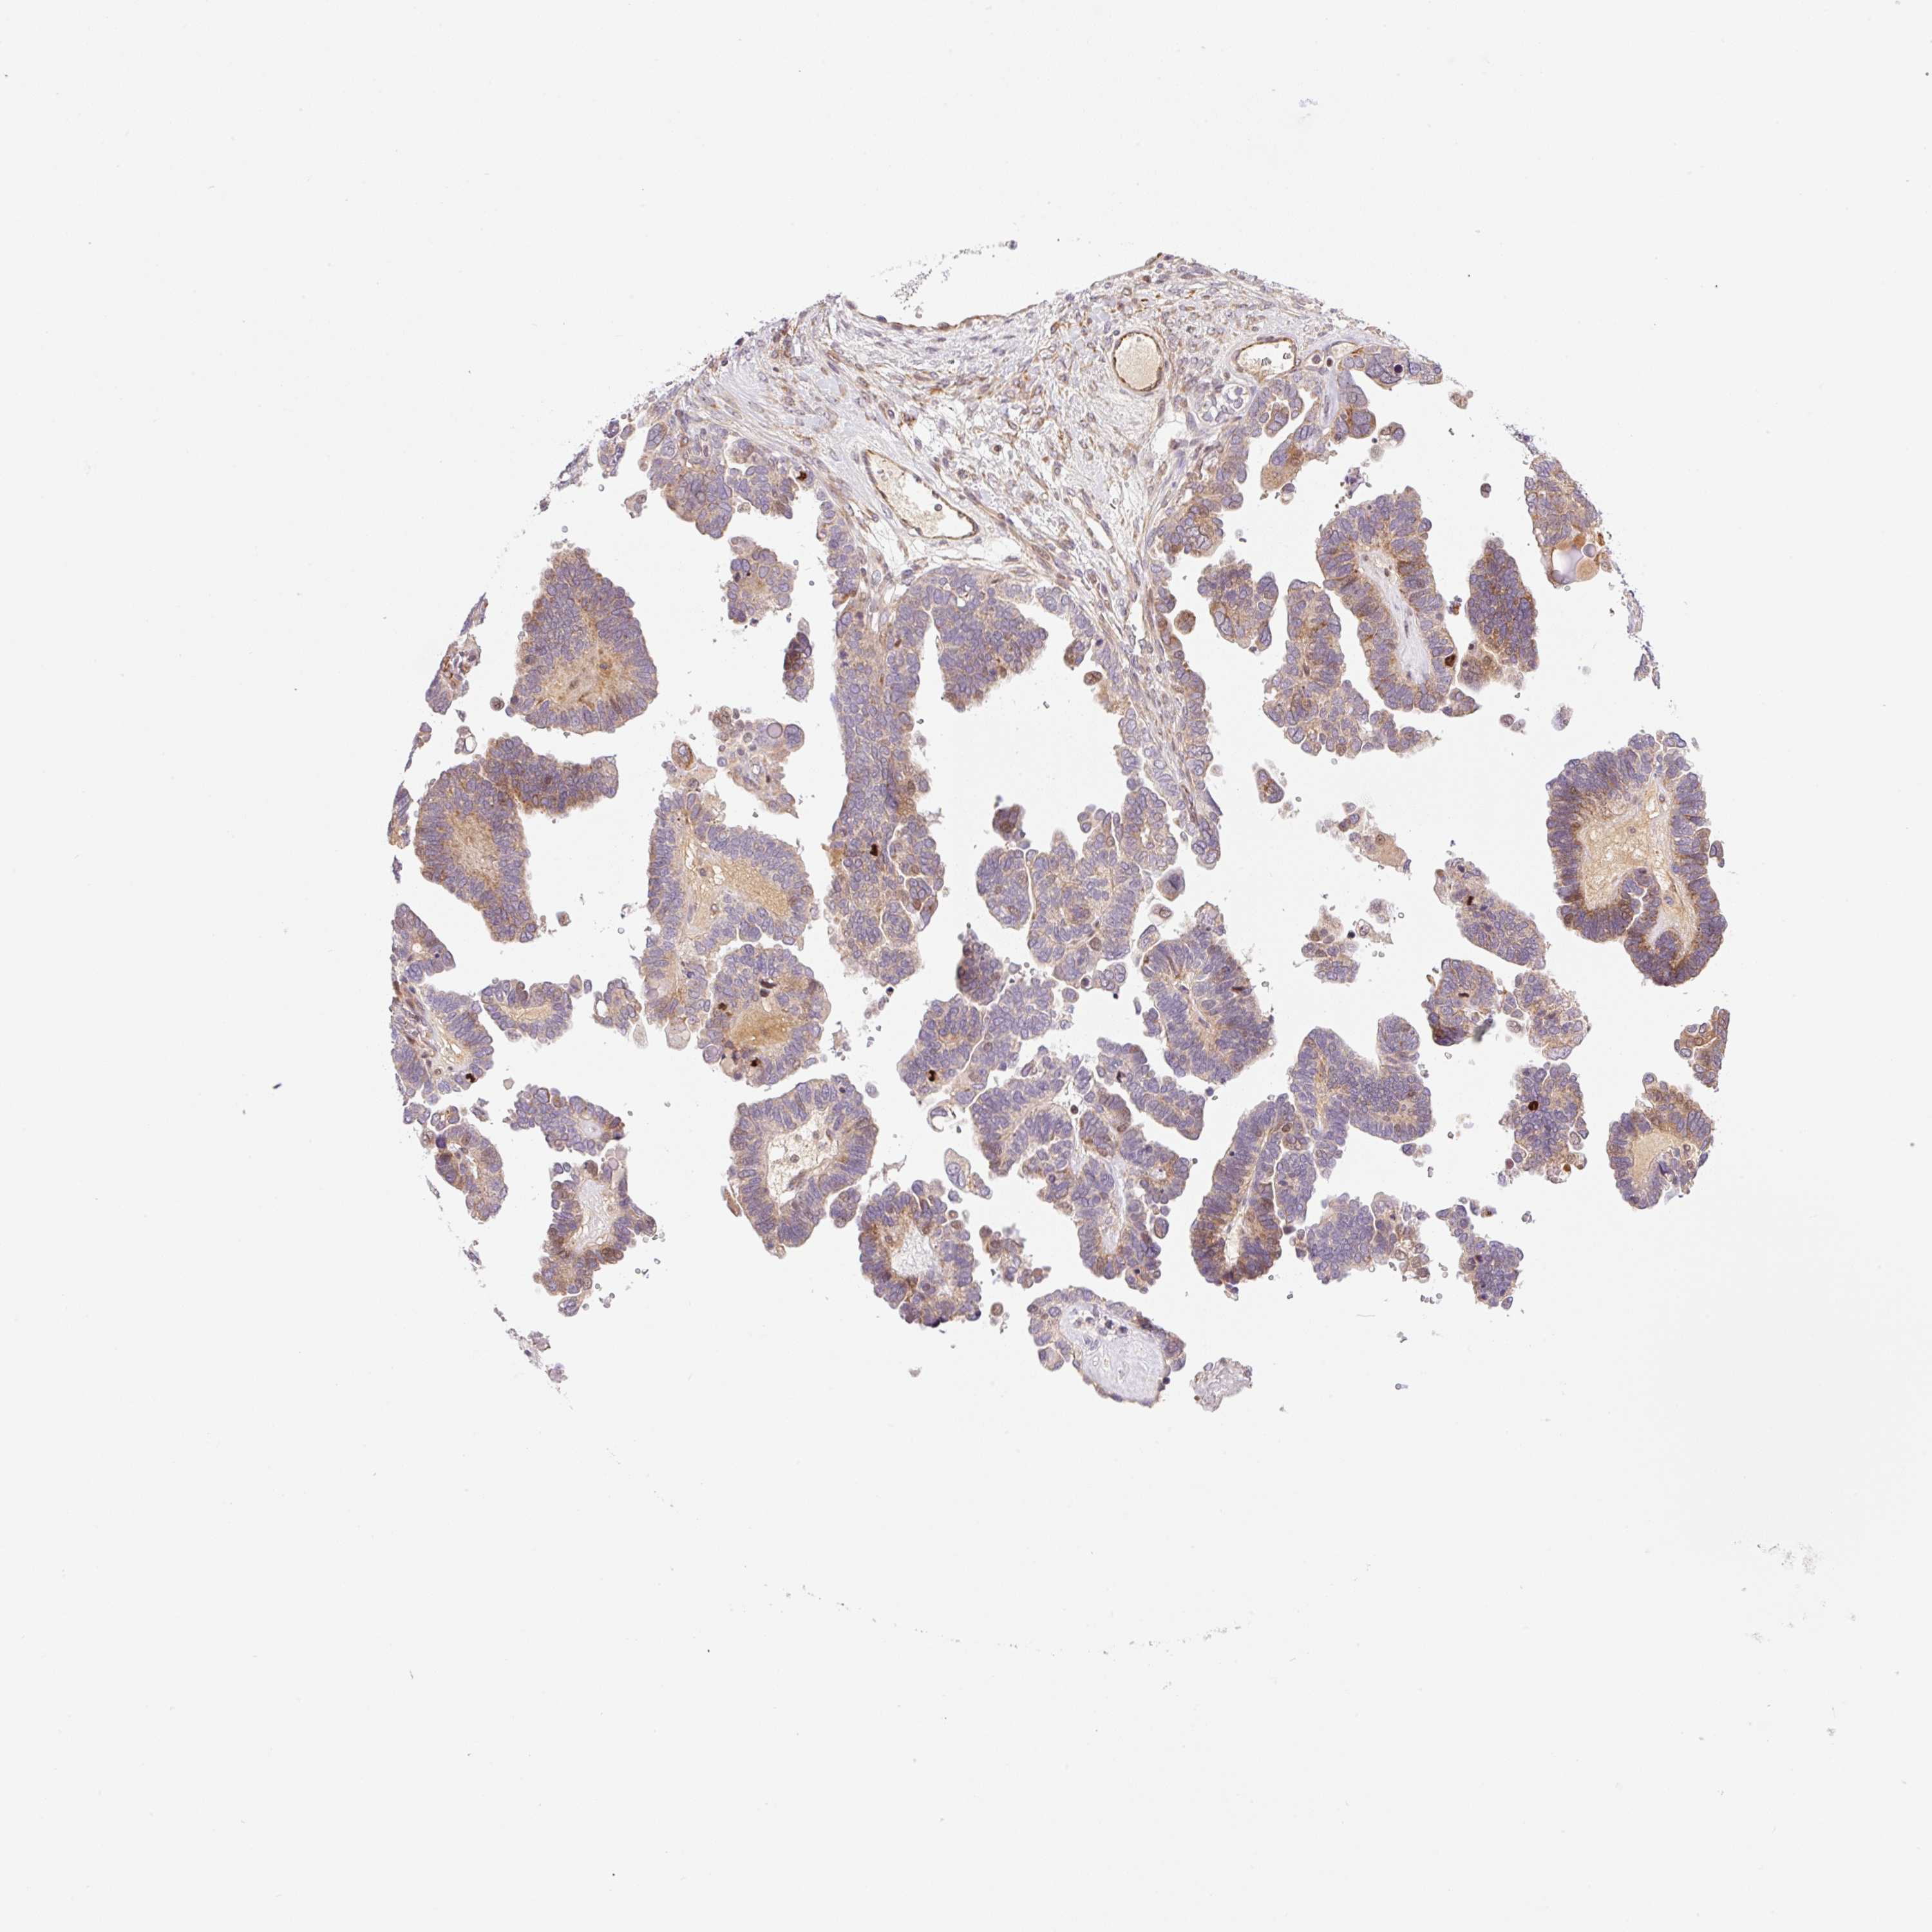

OVARIAN CANCER - Protein expressioni

A mouse-over function shows sample information and annotation data. Click on an image to view it in a full screen mode. Samples can be filtered based on level of antibody staining by selecting one or several of the following categories: high, medium, low and not detected. The assay and annotation is described here.

Note that samples used for immunohistochemistry by the Human Protein Atlas do not correspond to samples in the TCGA dataset.

Antibody stainingi

Antibody staining in the annotated cell types in the current human tissue is reported as not detected, low, medium, or high, based on conventional immunohistochemistry profiling in selected tissues. This score is based on the combination of the staining intensity and fraction of stained cells.

Each image is clickable and will lead to virtual microscopy that enables deeper exploration of all samples and also displays staining intensity scores, fraction scores and subcellular localization as well as patient and tissue information for each sample.

Antibody HPA051421

Antibody HPA054639

Staining

High

Medium

Low

Not detected

Intensity

Strong

Moderate

Weak

Negative

Quantity

>75%

75%-25%

<25%

None

Location

Nuclear

Cytoplasmic/membranous

Cytoplasmic/membranous,nuclear

Cystadenocarcinoma, serous, NOS

Cystadenocarcinoma, mucinous, NOS

Adenocarcinoma, NOS

Carcinoma, endometroid